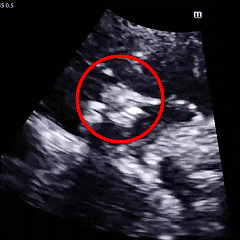

术后1个月及3个月复查时超声提示:房间隔可见封堵器回声,封堵器“三明治”结构完整,轮廓清晰,位置固定,无残余分流,无周围其他结构异常。

术后1月随访超声

术后3月随访超声

术后6个月复查超声显示:封堵器轮廓模糊,逐渐降解,“三明治”轮廓模糊。TCD发泡试验结果转为阴性,提示右向左分流消失,介入治疗效果显著。

术后6月随访超声